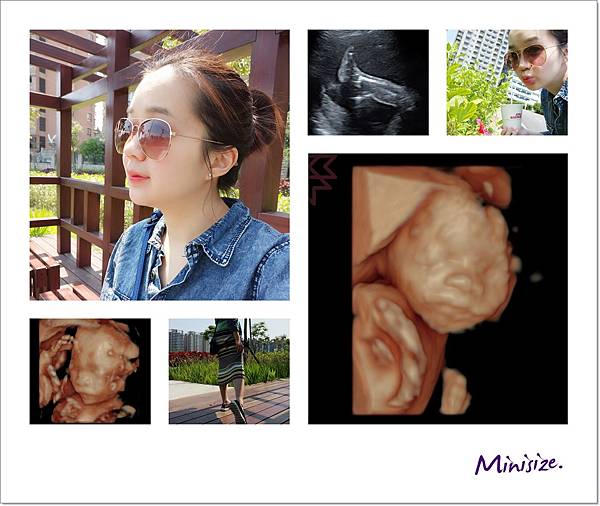

進入高層次超音波檢查吧

高層次超音波為2D檢查

建議安排在妊娠的2024週進行

此時寶寶大小羊水量最為適中

週數太小,有時胎兒心臟血管影像細節會比較不清晰

週數過大,因胎兒骨頭鈣化越來越明顯,遮擋了在骨頭後的影像

加上胎兒活動空間變小,姿勢不佳則會增加檢查的困難

我們在一個月前預訂禾馨民權婦幼診所自費做高層次超音波

22週時特別請了一天產檢假前往進行檢查 費用4200

我選取幾張比較有趣的超音波照片解說就好

脊椎

骨骼要呈現排列整齊相互對稱

背部皮膚的表層也要光滑 完整連接

腦

箭頭處為透明中膈要明顯

左右腦也要對稱

性別

一樣是男生

面

一直很期待看到寶寶的長相

究竟是像爸爸還是麻麻?!

爸媽綜合體又會呈現什麼樣子

也許寶寶想保留一點神祕感

這是唯一張好好配合拍照的

大大的鼻子、嘴巴好福氣!!

我們的Timo寶寶檢查數據都正常 很健康唷!

順便做個寶寶自我介紹

我們寶寶的英文名字是 Timothy

簡稱或小名叫作 Timo

預計在今年夏季八月底出生

他也很期待跟大家見面 常常在肚皮開Party 跳舞呢